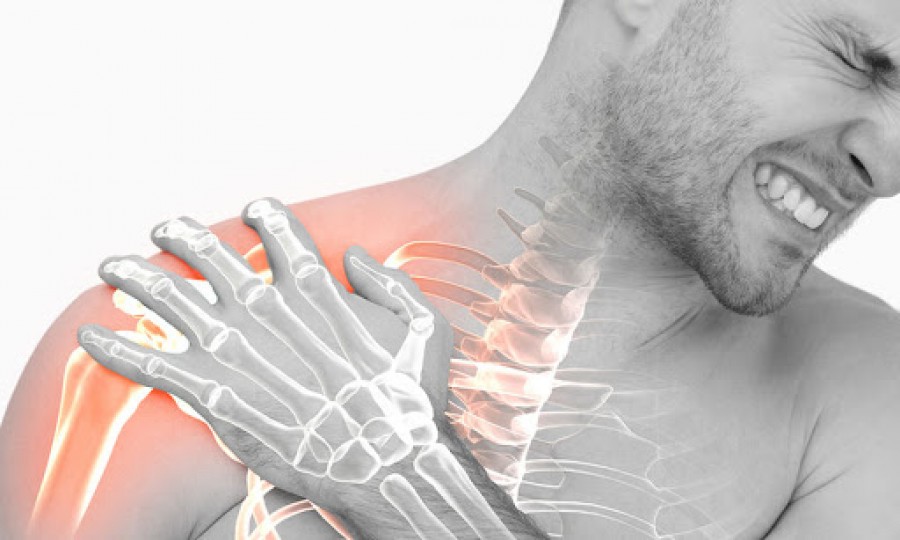

Ο πόνος στον ώμο είναι ένα πρόβλημα που ταλαιπωρεί εκατομμύρια ανθρώπους στον κόσμο και μπορεί να καταστήσει δυσλειτουργικό όλο το χέρι, κάνοντας την εκτέλεση των καθημερινών δραστηριοτήτων σχεδόν αδύνατη.

Οι ώμοι μας είναι επιρρεπείς σε τραυματισμούς, καθώς αναλαμβάνουν να κάνουν το μεγαλύτερο έργο στις περιστροφικές κινήσεις των χεριών.

Ο πόνος στον ώμο μπορεί να υπάρχει σε ηρεμία, να εμφανίζεται με τις κινήσεις, να επιδεινώνεται τη νύχτα ή να είναι συνεχόμενος και να συνοδεύεται από αστάθεια, δυσκαμψία ή και μυϊκή αδυναμία, εξηγεί ο κ. Αναστάσιος Δεληγεώργης, Aναπληρωτής Διευθυντής Γ’ Ορθοπαιδικής Κλινικής νοσοκομείου ΥΓΕΙΑ, Eξειδικευμένος ορθοπαιδικός χειρουργός γόνατος, ώμου & ισχίου, Πιστοποιημένος Αθλητίατρος από τη Διεθνή Ολυμπιακή Επιτροπή, (https://tasosdeligeorgis.gr/).

Οι ώμοι μας είναι επιρρεπείς σε τραυματισμούς, καθώς αναλαμβάνουν να κάνουν το μεγαλύτερο έργο στις περιστροφικές κινήσεις των χεριών.

Ο πόνος στον ώμο μπορεί να υπάρχει σε ηρεμία, να εμφανίζεται με τις κινήσεις, να επιδεινώνεται τη νύχτα ή να είναι συνεχόμενος και να συνοδεύεται από αστάθεια, δυσκαμψία ή και μυϊκή αδυναμία, εξηγεί ο κ. Αναστάσιος Δεληγεώργης, Aναπληρωτής Διευθυντής Γ’ Ορθοπαιδικής Κλινικής νοσοκομείου ΥΓΕΙΑ, Eξειδικευμένος ορθοπαιδικός χειρουργός γόνατος, ώμου & ισχίου, Πιστοποιημένος Αθλητίατρος από τη Διεθνή Ολυμπιακή Επιτροπή, (https://tasosdeligeorgis.gr/).